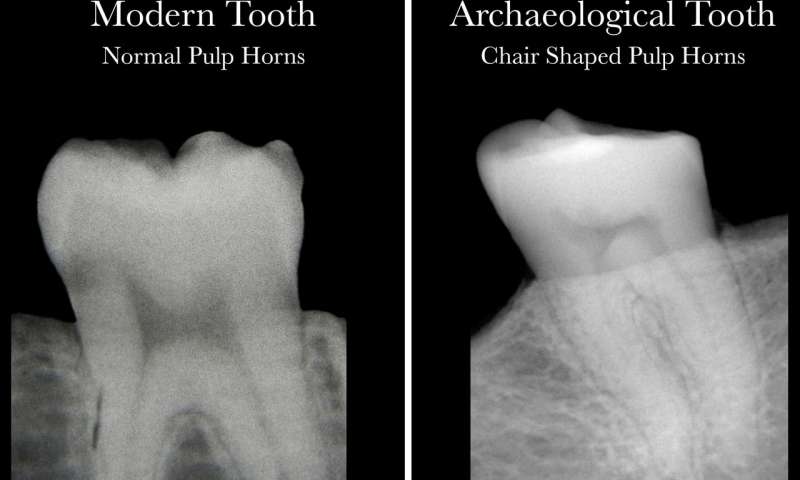

Τώρα οι ερευνητές από τον Καναδά προσπάθησαν να ξεπεράσουν αυτούς τους «σκοπέλους» αναζητώντας άλλους τρόπους μελέτης των δοντιών. Χρησιμοποίησαν έτσι την απλή ακτινογραφία για να εξετάσουν τα «πολφικά κέρατα» – εκείνη τη σκούρα σκιά στο κέντρο της εικόνας του δοντιού που γνωρίζει όποιος έχει κάνει ακτινογραφία στα δόντια. Εντόπισαν ένα μόνιμο, αναγνωρίσιμο μοτίβο το οποίο, όπως αναφέρουν, μπορεί να αποδειχθεί πολύτιμο όχι μόνο στη μελέτη των αρχαίων δοντιών αλλά και των δοντιών του καθενός μας βοηθώντας σημαντικά στη διάγνωση σχετικά με την ανεπάρκεια της βιταμίνης D.

Αριστερά μια ακτινογραφία υγιούς σύγχρονου δοντιού και δεξιά αρχαίο δείγμα δοντιού που μαρτυρεί την ανεπάρκεια βιταμίνης D. Στο υγιές δόντι ο πολφός σχηματίζει μια «αψίδα» με… αφτιά στο επάνω μέρος. Στο δόντι ατόμου με ανεπάρκεια βιταμίνης D το επάνω μέρος του δοντιού έχει ασύμμετρο σχήμα ενώ και οι δύο πλευρές της αψίδας σχεδόν ενώνονται

Το σχήμα του πολφού στα δόντια ενός υγιούς ατόμου μοιάζει με μια αψίδα με αφτιά στο πάνω μέρος της ενώ στα δόντια ενός ατόμου με σοβαρή ανεπάρκεια βιταμίνης D εμφανίζεται ασυμμετρία και οι δύο πλευρές της αψίδας φαίνεται σαν να ενώνονται. Σύμφωνα με την επικεφαλής της μελέτης, καθηγήτρια Ανθρωπολογίας στο Πανεπιστήμιο ΜακΜάστερ Μέγκαν Μπρίκλεϊ «τα ευρήματα αυτά είναι πολύ σημαντικά. Η μελέτη στόχευε περισσότερο στο να διερευνήσει μέσα από αρχαία δόντια το παρελθόν, αλλά εκτιμώ ότι έχει τη δυναμική να συμβάλλει και στο σήμερα βοηθώντας πολλά άτομα με ανεπάρκεια βιταμίνης D».